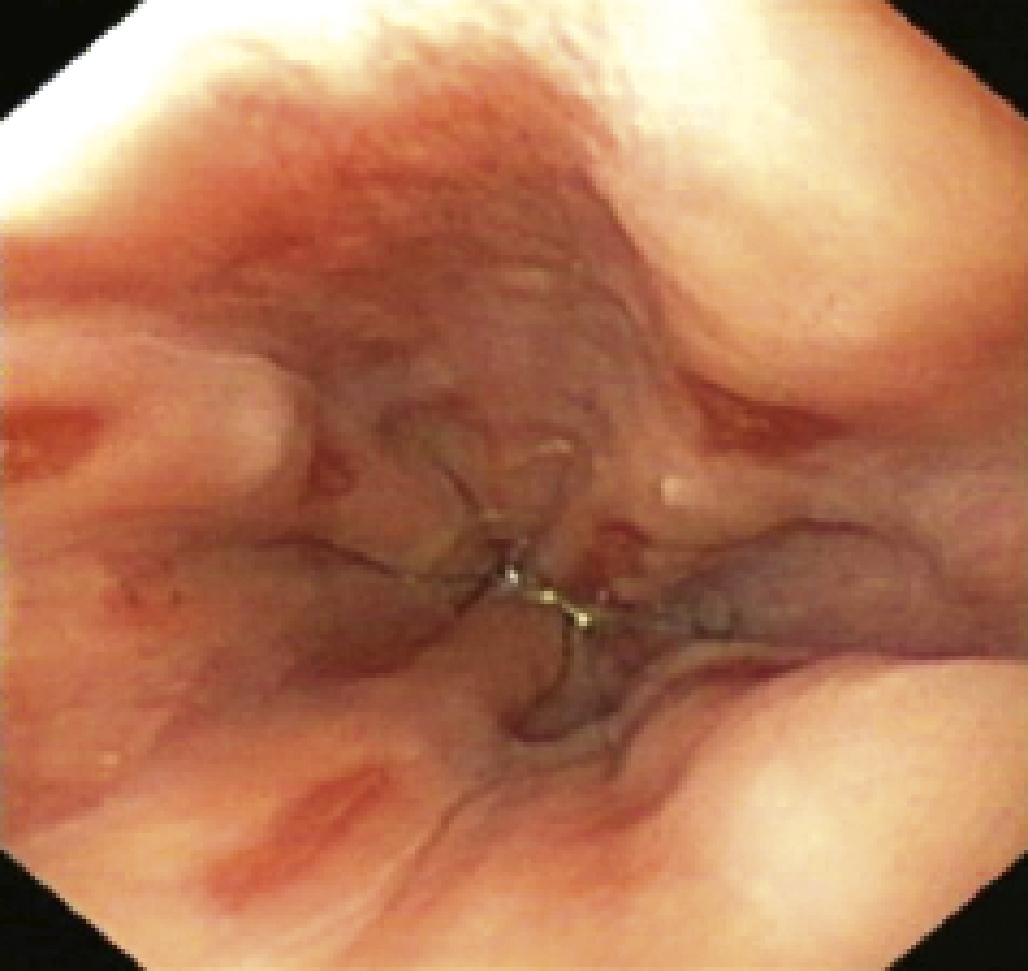

Une radiographie d’abdomen sans préparation (ASP), faite au moins une heure après la dernière tétée, montre un estomac qui reste plein avec un niveau hydro-aérique gastrique, associé à une rareté de l’aération du grêle. Cet abdomen sans préparation n’est plus recommandé depuis janvier 2009 par la Haute Autorité de santé (HAS). Le diagnostic repose sur l’échographie abdominale (fig. 1) qui montre l’olive pylorique avec une image en cible (coupe transversale) ou en sandwich (coupe longitudinale). Les mensurations du muscle pylorique sont augmentées (longueur > 17 mm, diamètre total > 13 mm, épaisseur musculaire > 4 mm). L’estomac est en stase avec de rares passages transpyloriques. En cas de mensurations limites, l’échographie sera refaite après 24 ou 48 heures montrant alors des signes plus francs. Le transit œsogastroduodénal n’est plus réalisé pour le diagnostic de sténose du pylore.

• douleur rétrosternale lors de l’alimentation, voire hématémèse et anémie, qui font évoquer une œsophagite (fig. 2) ;